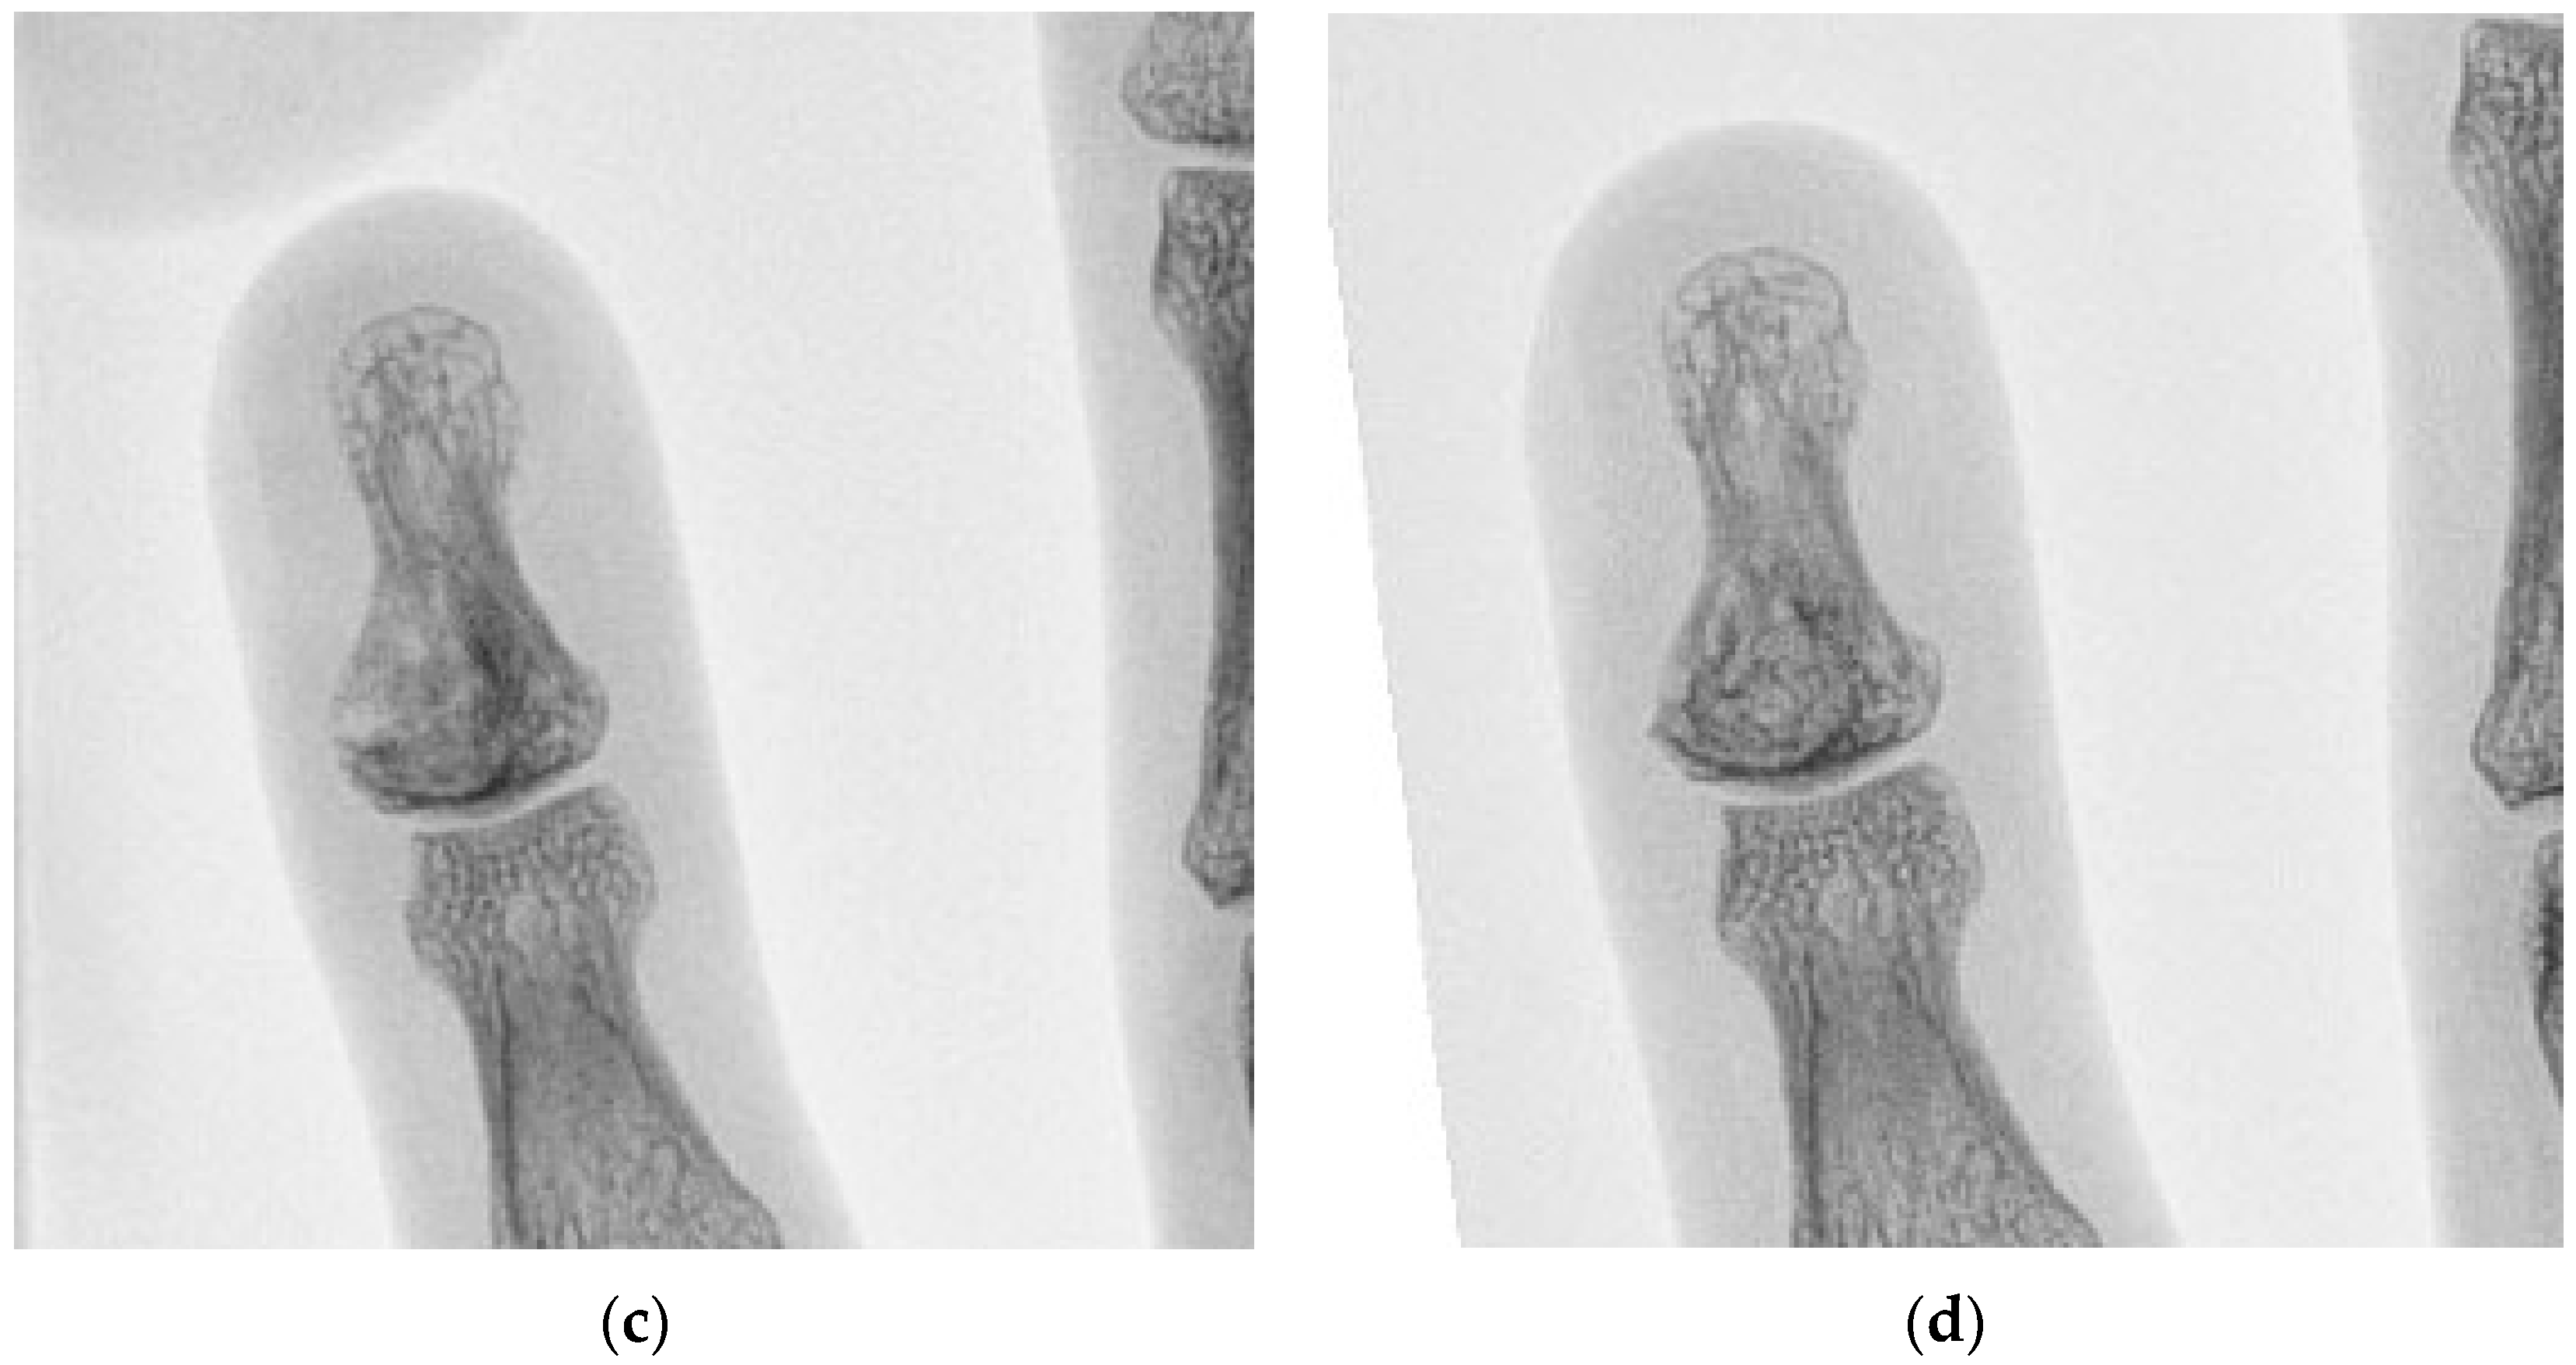

5 | 36 M | 1 | Left little finger P3 | 10 | Enchondroma | 25 |

7 | 71 M | 2 | Right middle finger P3 | 20 | Epidermoid cyst | 27 |